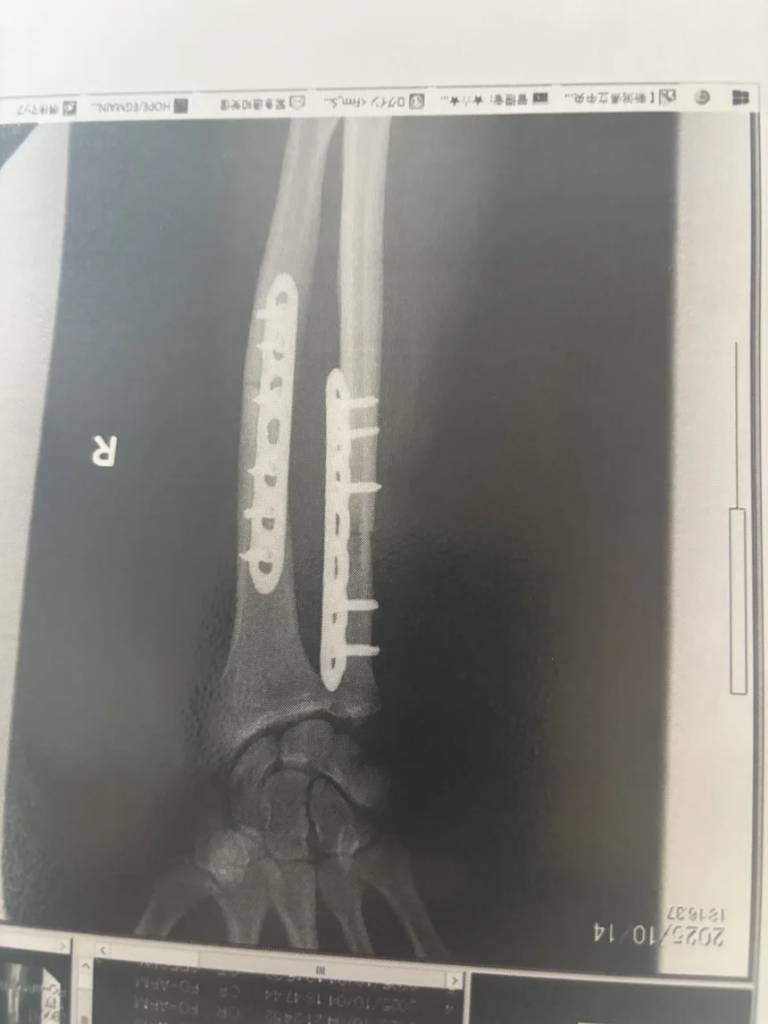

Halloran在病床上接受CNN訪問時透露,他已接受了3次手術治療,包括進行骨移植以填補被咬斷的骨頭,以及在手臂裝入金屬板固定。雖然手臂斷裂、腳部嚴重受傷,但他仍能跑約一公里與前來接應的妻子會合,並等待救護車到達。他坦言距離身體完全康復還有一段漫長時間,原本的馬拉松訓練計劃也被迫中斷。除了身體創傷外,這次襲擊也為他留下巨大的心理陰影,「就像滑浪手遭鯊魚襲擊後害怕回到海裡一樣」。不過他決定康復後會重返叢林跑步,並考慮攜帶熊噴霧作防身之用。